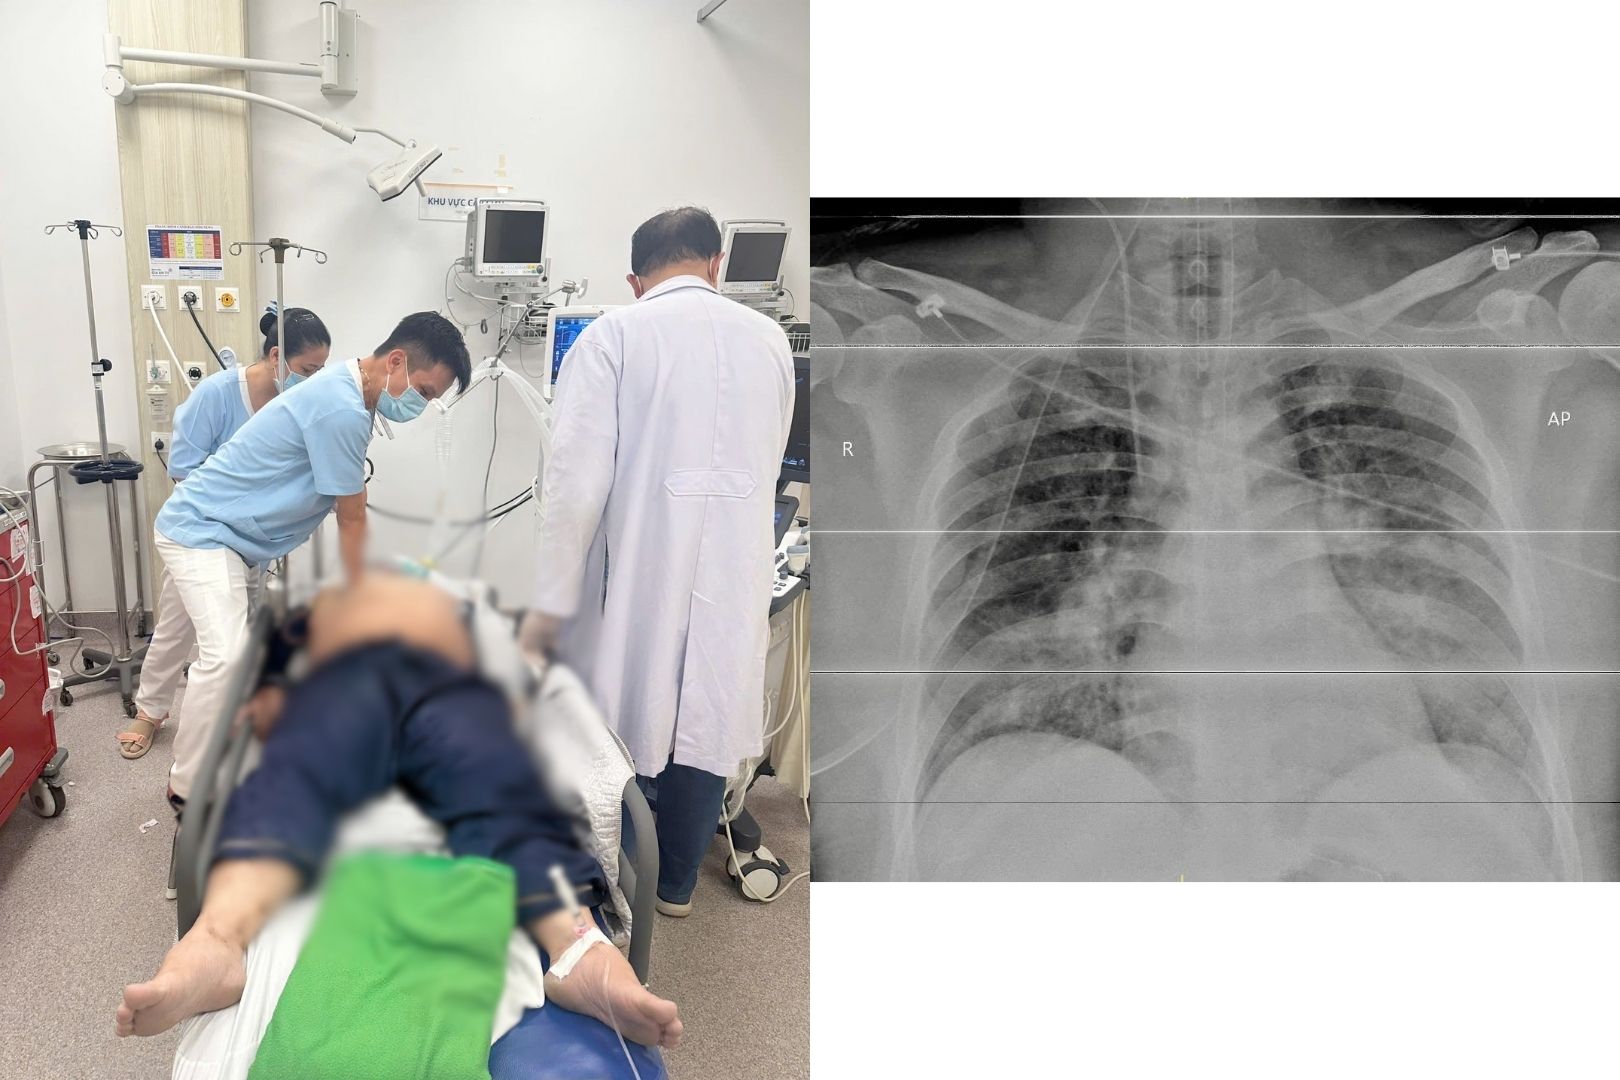

Bệnh viện Quân y 175 vừa cấp cứu thành công một bệnh nhân nhồi máu cơ tim cấp biến chứng rối loạn nhịp ác tính, ngừng tim nhiều lần nhờ phối hợp đa chuyên khoa và triển khai kỹ thuật hồi sinh tim phổi có hỗ trợ tuần hoàn ngoài cơ thể (E-CPR/ECMO).

Ngưng tim vì chủ quan với hen phế quản

BS.CK2 Nguyễn Thắng Nhật Tuệ – Trưởng khoa Cấp cứu Bệnh viện Gia An 115 vừa chia sẻ một trường hợp ngưng tim, ngưng thở được cứu sống trong gang tấc, để lại nhiều cảnh báo đáng suy ngẫm cho cộng đồng.